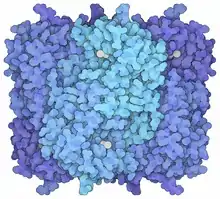

One of the main causes for the pathology of lead is that it interferes with the activity of an essential enzyme called delta-aminolevulinic acid dehydratase, or ALAD (see image of the enzyme structure), which is important in the biosynthesis of heme, the cofactor found in hemoglobin.[187][188][189] Lead also inhibits the enzyme ferrochelatase, another enzyme involved in the formation of heme.[23][190] Ferrochelatase catalyzes the joining of protoporphyrin and Fe2+ to form heme.[23][30] Lead's interference with heme synthesis results in production of zinc protoporphyrin and the development of anemia.[191] Another effect of lead's interference with heme synthesis is the buildup of heme precursors, such as aminolevulinic acid, which may be directly or indirectly harmful to neurons.[192] Elevation of aminolevulinic acid results in lead poisoning having symptoms similar to acute porphyria.[193][194][195][196][197]

Neurons